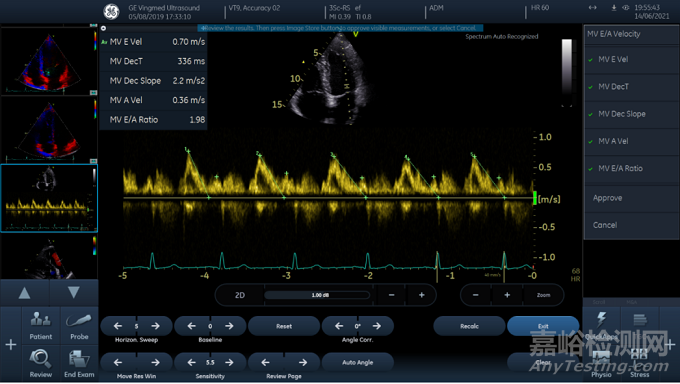

圖1 頻譜自動識別功能用戶界面

圖1為頻譜自動識別功能的用戶界面,使用頻譜自動識別功能后,圖像區(qū)域右上角會有明確提示:Spectrum Auto Recognized,并且操作界面頂部會提醒用戶審核自動測量結果(Review the results. Then press Image Store button to approve visible measurements, or select Cancel)。在右側測量菜單底部用戶可以選擇Approve或者Cancel。點擊Approve后,系統(tǒng)會接受自動測量結果;點擊Cancel后,用戶可直接進行手動測量或選擇別的測量項目。